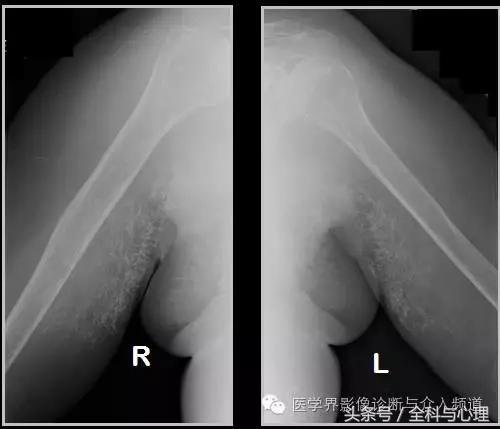

六、肌腱钙化/滑囊炎并钙化

肩关节最常见:肱二头肌长头、肩峰下滑囊钙化,可伴有急性疼痛、肿胀,局部压痛。

软组织钙化与骨化,软组织钙化和骨质增生 肱二头肌肌腱钙化(肩周炎)

软组织钙化与骨化,软组织钙化和骨质增生 肩周炎

软组织钙化与骨化,软组织钙化和骨质增生 大粗隆滑囊炎